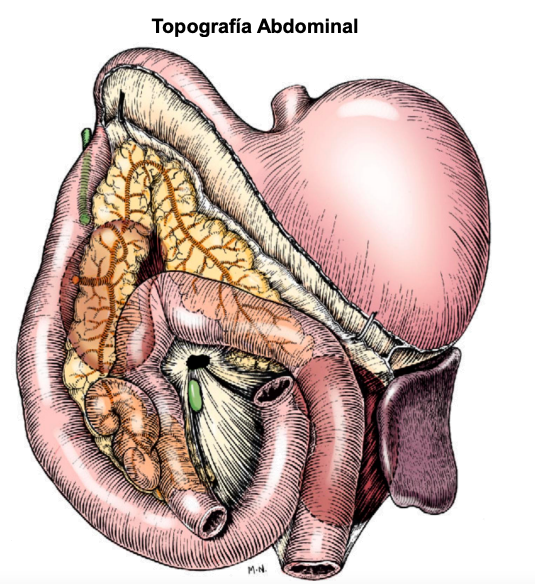

Bases anatómicas - Abdomen

esofago no se ve en radiografias. De craneal a caudal:

- Higado vesicula biliar a la derecha

- Estomago con pancreas

- Bazo (fundus a la izquierda, cola a la derecha en perros, gatos se mantiene medio-izquierdo)

- intestinos (asas intestinales) Colon ascendente derecho, descendente izquierdo